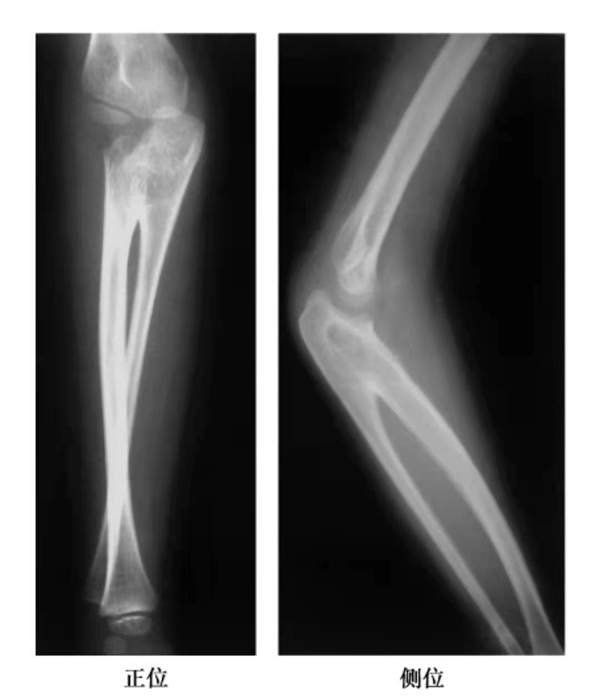

Ⅰ型:真正的桡尺骨连接,或无头型。表现为桡骨头缺如,有桡尺骨间骨性融合(图5-5)。

图1 近侧尺桡关节融合X线片